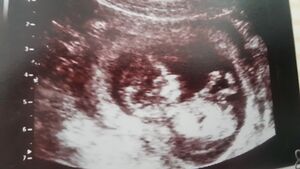

| − | [[Datei: | + | [[Datei:Fötus Embryo Ultraschall 2.jpg|thumb|300px|right|{{ImageCaption|Titel=Gegen Ende des 3. Monats spricht man nicht mehr von einem Embryo sondern von einem Fötus.|Urheber=Wingrid Weidinger|Quelle={{ImageMetaSource|Quelle=https://kiwithek.wien/index.php/Datei:SW13.jpg|Linktext=}}|Lizenz={{ImageMetaLicense|URL=https://creativecommons.org/licenses/by-nc-sa/3.0/at/|Lizenz=CC BY-NC-SA 3.0 AT}}}}]] |

Ende des 3. Monats spricht man nicht mehr von einem Embryo sondern von einem Fötus. Er ist schon etwa 8 cm groß.

Gegen Ende des 4. Monats entwickeln sich die Geschlechtsorgane. Wenn das Baby richtig liegt, kann man bei einer Ultraschalluntersuchung erkennen, ob ein Bub oder ein Mädchen geboren wird.